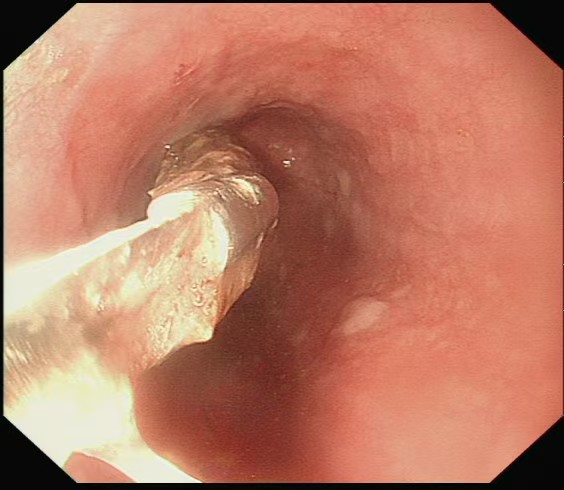

面对危急情况,高新生主任团队凭借丰富的临床经验和成熟的内镜技术,借助透明帽辅助清晰暴露视野,再用异物网篮精准抓取枣核,成功避开其锋利边缘,将这枚 “致命异物” 完整取出。随后,医生用钛夹如同 “内部缝合针”,牢牢封闭了溃疡创面。经过 5 天的住院观察,赵大娘腹痛症状明显缓解,复查结果正常后顺利出院。